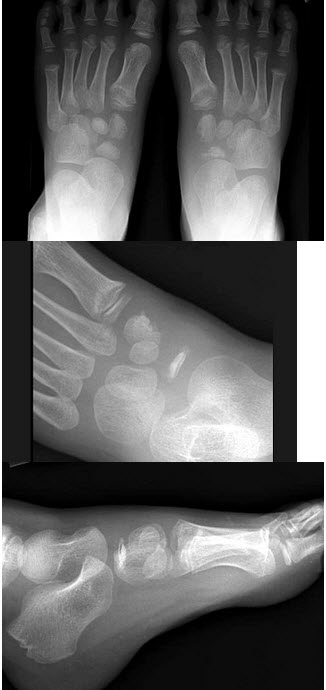

244、单项选择题

男,5岁,足背肿痛,结合图像,最可能的诊断是()

A.跗舟骨缺血坏死

B.跗舟骨骨折

C.成骨不全

D.软骨发育不全

E.剥脱性骨软骨炎

点击查看答案